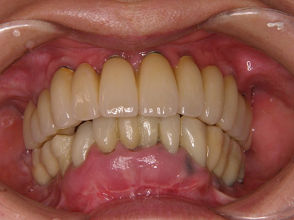

52歳女性:外傷後の上顎全部に自家骨移植を行いインプラント治療を行った症例(当院補綴科との連携症例)。